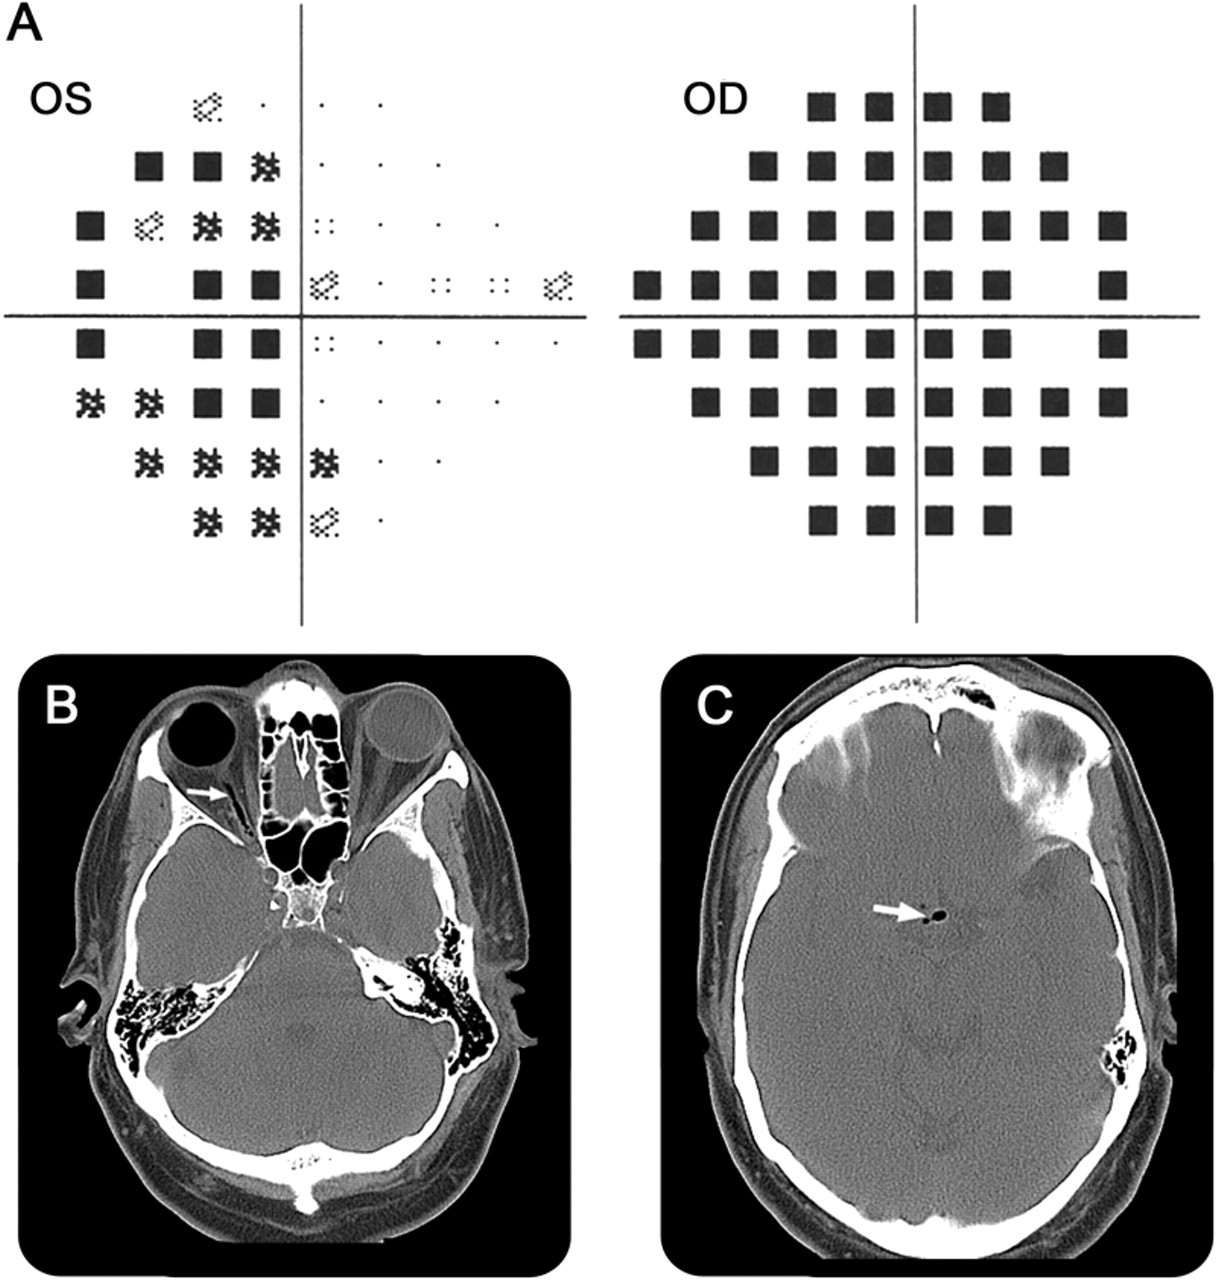

视野测量测试和CT成像

(一)视野测量测试证明减少敏感性在时间领域的左眼视网膜脱离(侧)。(B, C) CT扫描显示在正确的全球天然气,跟踪从右侧视神经视交叉(箭头)。天然气也存在于侧脑室。